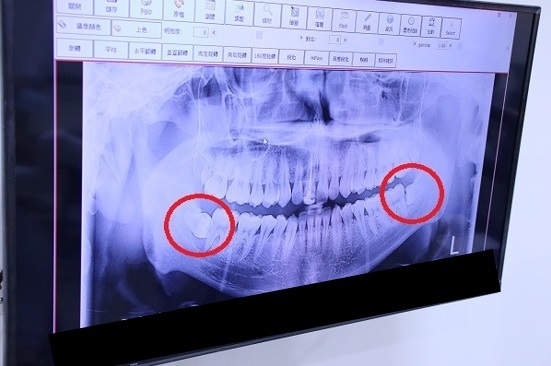

x光機掃描口腔,牙齒生長排列的樣子一覽無遺。

雲康植牙醫師評估植牙風險,植牙醫師會因為你平常的生活習慣、年紀、口腔是否健康狀態來評估若要植牙是不是要先治療牙周病或是做其他治療。